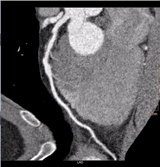

Figure 1(a).

Initial interpretation suggested the presence of a two-vessel disease: There was plaque in the proximal left anterior descending (LAD) (the curved multi-planar reformation is shown in Figure 1a) and also the mid-portion of the right coronary artery (RCA) (the curved multi-planar reformation is shown in Figure 1b). Myocardial Defect Assessment was performed. (An overview of the results is shown in Figure 2.)